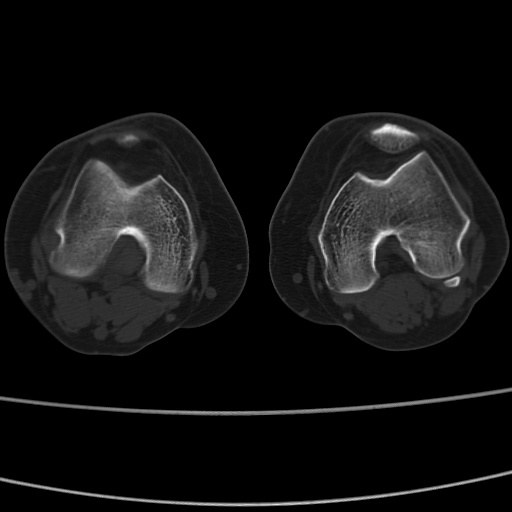

女性,50岁。【请提供患者临床症状体征】

右膝关节退行性改变,关节游离鼠。

右膝关节退行性改变,滑膜黏液囊钙/骨化并游离。